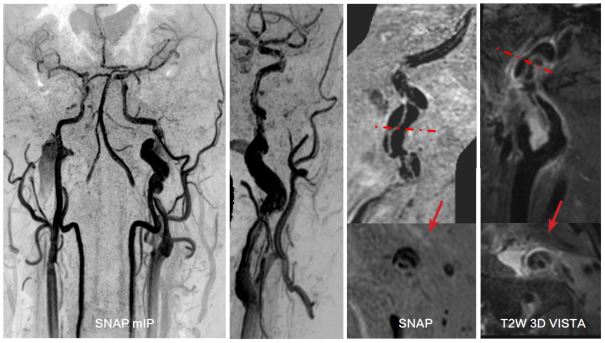

高分辨血管壁成像技术清晰显示椎动脉及基底动脉粥样硬化并斑块形成至管腔狭窄 磁共振高分辨血管壁成像技术显示左侧大脑中动脉 M1 段内血栓致左侧大脑梗塞

磁共振高分辨血管壁成像技术清晰显示左侧大脑中动脉 M1 段炎性增强及管腔狭窄 左侧颈内动脉路外段动脉夹层,可观察到真假腔、内膜片和周围炎性渗出 磁共振大范围高分辨血管壁多对比度成像技术